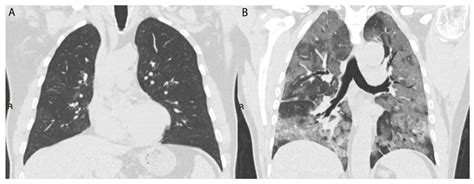

Cryptogenic Organizing Pneumonia: Evolution of Morphological Patterns ...

mdpi.com